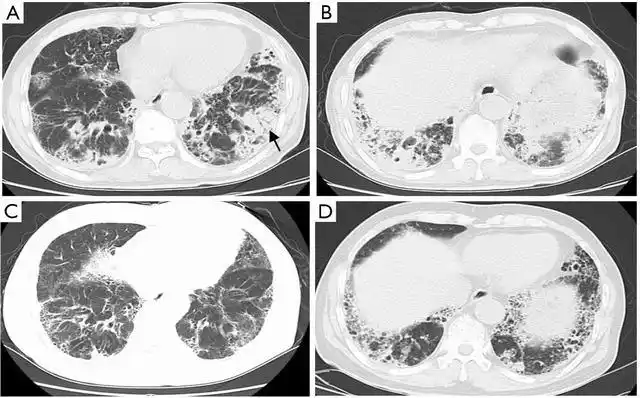

qims之窗 (014): 活动性肺结核的几种不典型ct表现及机制